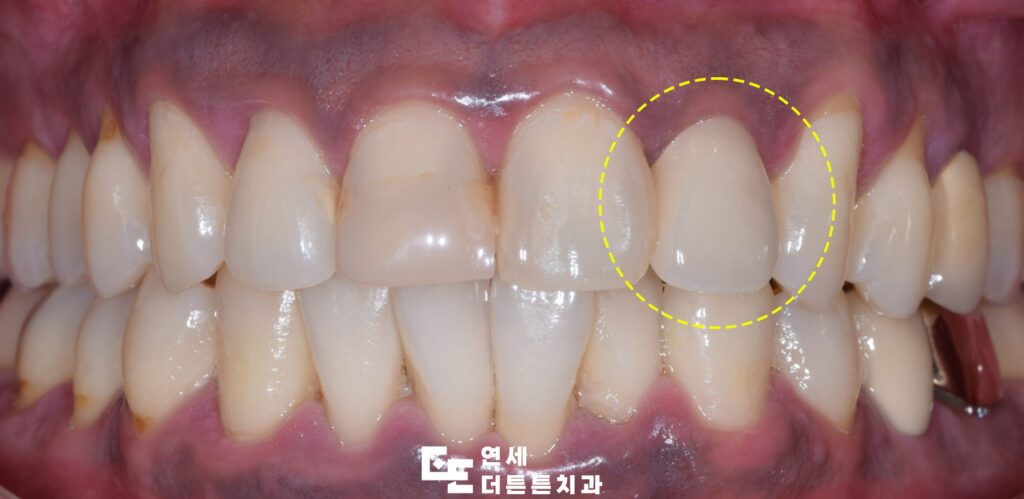

환자분께서는 떼워놓은 앞니가 까맣게 보이신다며 내원해 주셨는데요. 까맣게 보이신다고 말씀해 주셨던 왼쪽의 앞니는 이미 충치로 인해 레진으로 수복되어 있는 상태였고 그 아래로 2차 충치가 발생하여 까맣게 보이고 있는 상태로 이미 넓은 범위가 떼워져 있어 모두 제거하고 크라운 수복을 진행하기로 하였습니다.

앞니 크라운 치료를 마친 후 사진입니다.